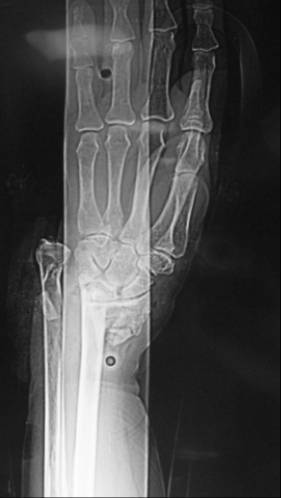

患者王某,老年女性,80岁,主因摔伤致左腕开放性骨折急症于2010年3月入院。查体:患者左侧腕关节处尺骨茎突哆出,掌侧皮肤裂伤,长约6cm,肌腱及皮下组织外露,左腕关节畸形。入院诊断为左侧腕关节开放伤(图1a);左侧桡骨远端骨折;左侧腕关节脱位(图1b)。于入院当日急症臂丛麻醉下行左腕伤口清创缝合术,左侧尺腕关节复位内固定术,左侧桡骨远端骨折复位内固定术(图2)。手术过程顺利,术后患者恢复良好,约术后5周拔除左侧腕关节固定克氏针,后患者自动出院。出院后1日患者因突发喘憋,进行性加重再次就诊于我院,血气分析示PO2 36.3mmHg,PCO2 30.4mmHg,D-二聚体4000ng/ml,胸CT示左下肺大片高密度影,肺通气灌注扫描显像提示双肺多发节段灌注缺损。入院诊断为:I型呼吸衰竭;肺栓塞;冠心病;高血压病3级;糖尿病2型;左桡骨远端骨折。给予速碧林 4100IU/d经验性抗凝治疗。第2日患者喘憋症状明显缓解,自诉无呼吸困难,动脉氧分压升至141mmHg(鼻导管吸氧5L/分)。应用速碧林3日后加用华法令5mg /d,间断复查KPTT及INR,华法令与速碧林重叠应用5日后,患者PT延长至18.9s,即停用速碧林,单独应用华法令,1周后患者好转出院。

图1 b、患者术前X线片,左侧桡骨远端骨折;左侧腕关节脱位